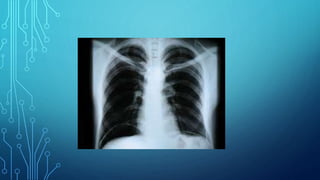

Radiography. This is atechnique of X-ray examination, in which a static image of an object is obtained, recorded on any information carrier: X-ray film, photographic film, digital detector. Any anatomical area can be captured on radiographs. Pictures of the entire anatomical region (head, chest, abdomen) are called overview. Pictures showing a small part of the anatomical area are called sighting pictures.

Some organs areclearly visible in the images due to natural contrast (lungs, bones), others (stomach, intestines) are clearly visible on radiographs only after artificial contrast. Passing through the object of study, X- rays are delayed. Where the radiation is delayed more, shading areas are formed. Where there is less - enlightenment.

X-ray images canbe positive and negative. In a negative image, bones appear light, air appears dark, and in a positive image, vice versa.